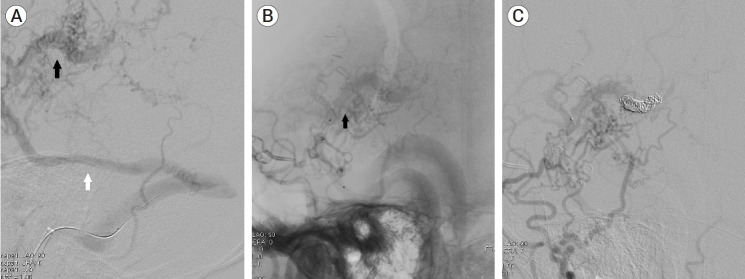

Craniotomy is known as a cause of iatrogenic dural cerebral arteriovenous fistula (AVF). However, mixed pial and dural AVFs after craniotomy are extremely rare and require accurate diagnosis and prompt treatment due to their aggressiveness. We present a case of an iatrogenic mixed pial and dural AVF diagnosed 2 years after pterional craniotomy for surgical clipping of a ruptured anterior choroidal aneurysm. The lesion was successfully treated using single endovascular procedure of transvenous coil embolization through the engorged vein of Labbe and the superficial middle cerebral vein. The possibility of the AVF formation after the pterional approach should always be kept in mind because it usually occurs at the middle cranial fossa, which frequently has an aggressive nature owing to direct cortical venous or leptomeningeal drainage patterns. This complication is believed to be caused by angiogenetic conditions due to coagulation, retraction, and microinjuries of the perisylvian vessels, and can be prevented by performing careful sylvian dissection according to patient-specific perisylvian venous anatomy.